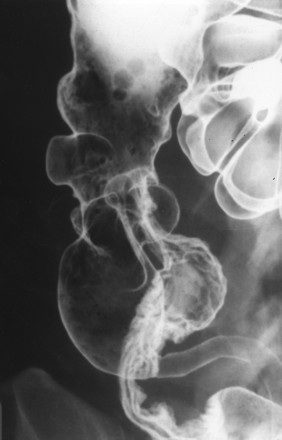

Viêm đại tràng do lao có hình ảnh giống bệnh Crohn, bệnh hiếm ở người da trắng nhưng hay gặp ở người châu Á và bệnh nhân AIDS. Mặc dù phần lớn là thứ phát sau lao phổi, nhưng đa số bệnh nhân không có bằng chứng lao phổi trước đó hoặc lao phổi hoạt động. Với bệnh nhân châu Á, phần lớn bệnh nhân lao ống tiêu hóa là do nuốt trực khuẩn lao bò. Chẩn đoán trực khuẩn kháng axit hoặc u hạt hoại tử bã đậu có độ nhạy thấp (khoảng 32% và 50%, tương ứng) [9]. Với sự hiểu biết tốt hơn về các đặc điểm của viêm lao đại tràng, chẩn đoán sớm bằng chụp cản quang kép là có thể [10]. Các đặc điểm sớm của lao đại tràng là co thắt, tăng tiết, tăng nhu động, tăng sản lympho, các nếp dầy, và các vết loét nông (Hình 18). Các dấu hiệu của viêm lao đại tràng tiến triển khi chụp cản quang kép bao gồm các vết loét ngang (Hình 19), các nốt, các nếp dầy, polyp viêm hoặc sau viêm, hẹp và biến dạng vùng hồi-manh tràng (Hình 20).

Hình 20. Bệnh nhân nữ 41 tuổi. Chụp cản quang kép cho thấy hẹp và biến dạng vùng hồi-manh tràng và đại tràng lên mà không thấy tổn thương niêm mạc hoạt động.